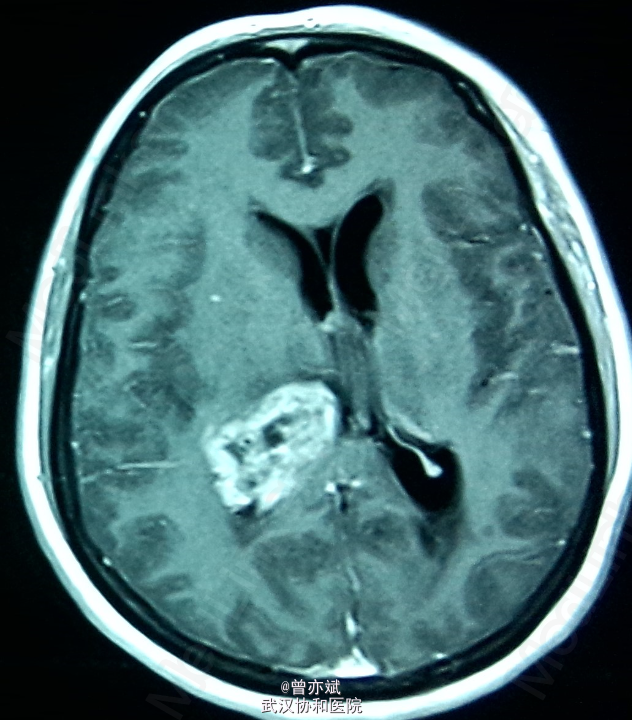

侧脑室占位一例

主诉:间歇性头痛半年余,加重一月 简要现病史:患者半年前无明显诱因出现间歇性头痛,无发热、恶心呕吐、肢体无力、抽搐等症状,近一月来,头痛症状加重,当地医院行MRI提示侧脑室占位。

专科查体神志清楚,双侧瞳孔等大等圆,直径约3mm,光反射灵敏,四肢肌力4级,生理反射村子啊,病理反射未引出。 MRI提示右侧 脑室巨大占位

诊断:右侧侧脑室占位:室管膜瘤? 处理:手术治疗